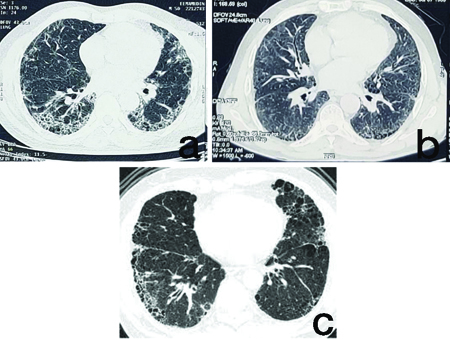

Out of the 3,012 patients, 10 patients were diagnosed with ILD. The median patient age was 51.5 years (range: 25-65 years). The median time for the development of respiratory symptoms from diagnosis of psoriasis was 24.5 months (range: 6-60 months). The median Forced Vital Capacity (FVC) percentage predicted was 58% (range: 32-85), and DLCO% predicted was 42% (range: 23-79) [Table/Fig-1]. All patients had chronic plaque-type psoriasis [Table/Fig-2]. The most common respiratory symptom at presentation was dry cough 6 (60%), followed by dyspnoea on exertion 4 (40%). Various serological testing and immunofluorescence assays to diagnose antibody patterns of various CTD were negative in all patients. A total of 5 (50%) patients had not previously or concomitantly been exposed to immunosuppressant, whereas 5 (50%) had been exposed. The most common immunosuppressants included methotrexate (n=4), followed by cyclosporine (n=1). Radiographic diagnosis were as follows: UIP pattern in 7 patients (70%, [Table/Fig-3a]), NSIP pattern in 2 patients (20%, [Table/Fig-3b]), and CPFE in 1 patient (10%, [Table/Fig-3c]). The [Table/Fig-4] demonstrates the demographic and clinical features of ILD patients with concomitant psoriasis.

HRCT Chest of psoriasis patients showing: (a) UIP pattern; (b) NSIP pattern; (c) CPFE pattern.

Immunological markers for collagen vascular diseases were negative in all patients. The mean FVC% predicted and DLCO% predicted were 58% and 42%, respectively, at the time of presentation. The mean decline in FVC values was mild (range: 32-85%) compared to DLCO values (23-79%), which showed very severe levels of impairment. This decline in FVC and DLCO was also observed in the study conducted by Ishikawa G et al., [10]. The study established that patients presented with mild impairment in FVC with a median of 69% predicted (range: 38-89%). On the contrary, the DLCO exhibited a more severe reduction, with a median of 47% predicted (range: 17-95%). Remarkably, compared to patients with Idiopathic Pulmonary Fibrosis (IPF), the decline in pulmonary function was relatively mild, as reflected by a subtle annual variation in predicted FVC%, ranging from -5.7% to +18%. We did not perform serial FVC and DLCO to see the performance of pulmonary function, as most of the patients were lost to follow-up. Radiological findings in 7 (70%) cases were consistent with a UIP pattern, NSIP pattern was seen in 2 (20%) cases and 1 (10%) had findings consistent with a CPFE pattern. A high incidence of severe fibrosis in the form of a UIP pattern indicated that the immune dysregulation triggered in psoriasis is severe and is much more than an inflammatory process.